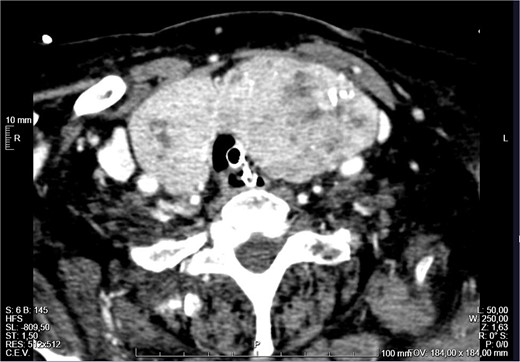

The patient remained monitored but a few hours later progressed with stridor and aggravated hypoxemia. An urgent nasopharyngoscopy was performed which showed significant laryngeal oedema and bulging of the posterior wall of the left hypopharynx. Despite systemic corticoid therapy, a decreased level of consciousness and desaturation lead to an orotracheal intubation. An urgent neck CT revealed a large multinodular goitre (RL 46 × 36 × 91 mm and LL 48 × 51 × 103 mm), with the superior pole of the left lobe ascending to the angle of the mandible, in a suprahyoid position, posterior to the submandibular gland (Fig. 1). The thyroid was extrinsically compressing the trachea and larynx, causing a deviation of the respiratory column to the right and narrowing of its lumen (Fig. 2). There was no apparent invasion of adjacent structures.

External compression of the thyroid and larynx by the mass with narrowing of its lumen.